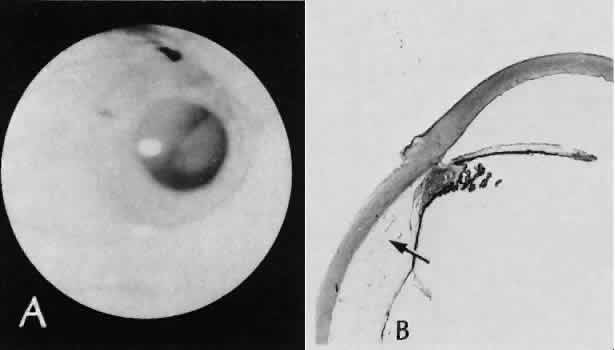

Fig. 28. A case of lens capsular rupture during intracapsular cataract extraction. On postoperative day 1 (inset 1), there was considerable retention of lens capsular material nearly obscuring the anterior chamber. By postoperative day 14 (inset 2), considerable clearing of debris has occurred. At 2 months following surgery (inset 3), the anterior chamber was nearly clear. The clearing of the debris was through the action of macrophages ingesting the cortical debris and exiting the eye through the trabecular apparatus. Macrophages filled with lens cortical material from a different case are seen in the main figure. (Periodic acid-Schiff stain; × 700.) (Yanoff M, Scheie HG: Cytology of human lens aspirate. Its relationship to phacolytic glaucoma and phacoanaphylactic endophthalmitis. Arch Ophthalmol 80:166–170, 1968.)